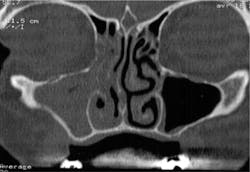

- First, is the sinus healthy or not? Starting from a CBCT prescribed by the implantologist and/or an endoscopic examination performed by the ENT, we must check the patency of ostium, which is the natural drainage pathway of the maxillary sinus. If the ostium is occluded (figure 3), the ENT will prescribe an adequate medical treatment and/or perform an endoscopic surgery (figure 4) in order to re-establish the patency. After this, clearance for sinus grafting will have to be given by the ENT.

Figure 3: The sinus ostium is blocked.

Figure 4: After an antrostomy, the ostium is patent.